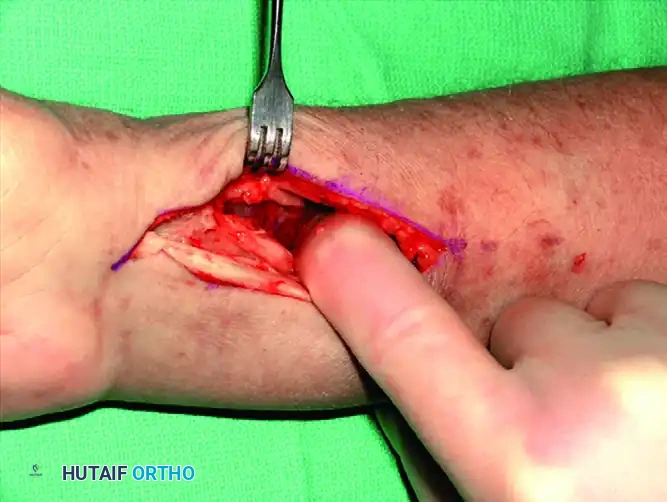

Deep Dissection: The floor of the FCR sheath is incised to access the deep compartment. The flexor pollicis longus (FPL) muscle belly is identified and partially detached or retracted ulnarly from the radius to expose the underlying pronator quadratus.

Pronator Quadratus Elevation: Using a Freer elevator or electrocautery, the pronator quadratus is elevated from its radial insertion in an L-shaped fashion, reflecting it ulnarly.

Fracture Exposure and Reduction: The fracture line is now fully exposed. Hematoma is evacuated, and the fracture is reduced under direct vision and fluoroscopic guidance.